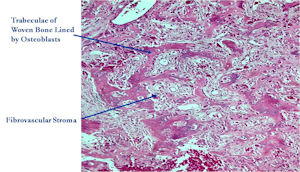

Microscopic Pathology

- Interlacing network of bone trabeculae in a loose fibrovascular stroma

- Prominent vessels

- Osteoblasts are plump, active, scattered mitotic figures

- Osteoblasts line up around periphery of trabeculae (Osteoblastic Rimming)

- Soft tissue component usually surrounded by shell of reactive bone or periosteum (Egg Shell Rim of Calcification)

- No cartilage production (as opposed to osteosarcomas that may contain areas of cartilage)